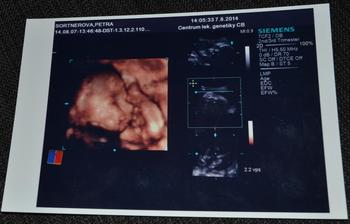

* 7.8.2014 - 4D ultrazvuk - jelikož je placenta na přední straně a Ellinka před sebou měla ještě pupeční šňůru a nohy, tak fotky nejsou nic moc... Ale nevadí. i tak je nádherná